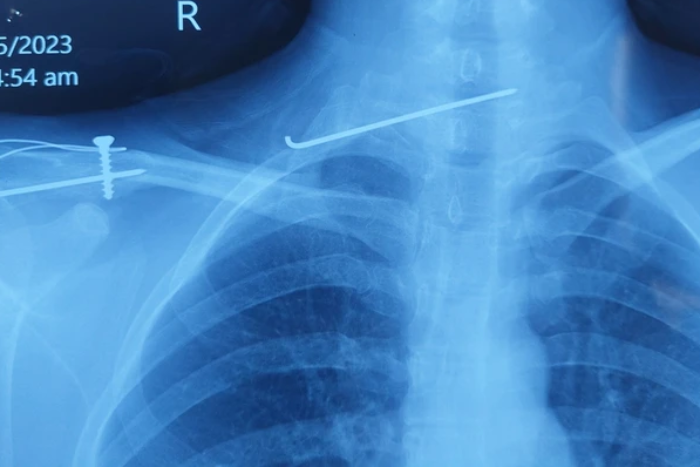

Bệnh nhân mắc hội chứng cổ rùa được thăm khám tại Bệnh viện 19-8. Ảnh: N. Huyền